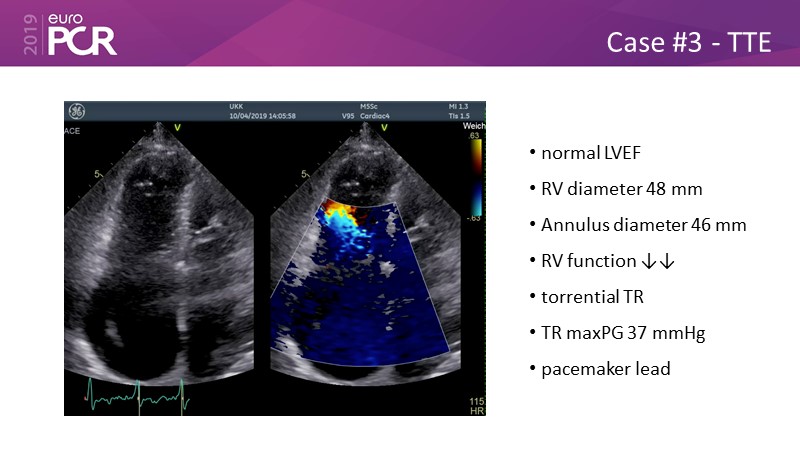

Addressing tricuspid regurgitation with annular reduction: the Cardioband tricuspid system

Consult this session to understand how patients with tricuspid regurgitation and annular dilatation can benefit from Cardioband system...

- To understand how patients with tricuspid regurgitation and annular dilatation can benefit from Cardioband system